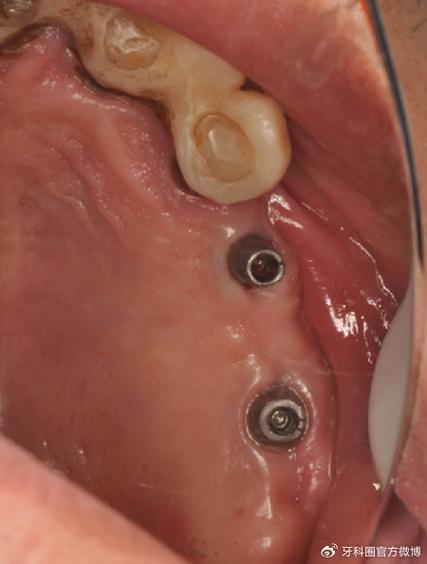

(图片来源网络,侵删)